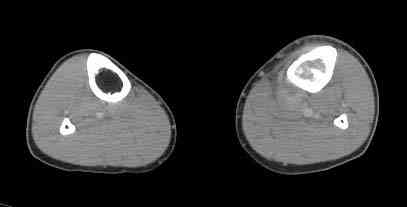

важаемые коллеги! Поступил больной 22 лет. Болен с января 2006 - появились боли в области верхнейтрети голени. При первичном осмотре в поликлинике был заподозрен первично-хронический остеомиелит - осмотрен гнойным хирургом - произведена биосия . Заключение - хондросаркома. Осмотрен онкологом - с учетом характера опухоли - химиотерапия, лучевое лечение не показано. Предложена либо ампутация, либо решение вопроса о возможности выполнения органосохраняющей операции. При обращении к нам произведена сцинтиграфия скелета - зоны гиперфиксации РФП: верхняя треть голени- 960%, нижняя треть бедра - 380%, Дистальный метафиз голени и затылочная область - 140%. В легких - метастазов нет. Произведена КТ (картинки в приложении). Учитывая абсолютную нестыковку рентгенологических и морфологических данных повторно биопсия. Выявлено, что первичная биопсия выполнялась из поверхностной параоссальной зоны - там локализованы хрящеподобные массы, далее очень плотная кость без хрящевых участков - биоптат взят фрезой с большим трудом. Морфологического заключения пока нет. Хотелось бы узнать Ваши варианты диагноза и соответственно тактику.